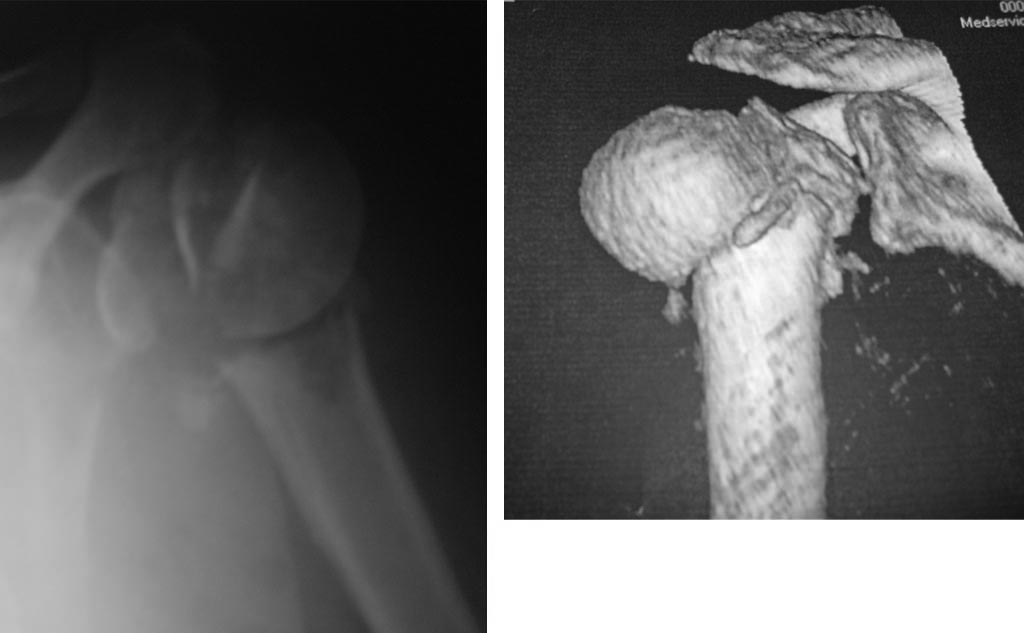

По R-грамме перелом левого плеча многофрагментарный,причем по

анатомической шейке, при этом головка плеча развернута на 180. Закрытая

репозиция безуспешна. Сопутствующие заболевания: гипертоническая

Подскажите, пожалуйста, что делать? Если синтез, то какой? Прилагаем

R-граммы и КТ в 3Д реконструкции